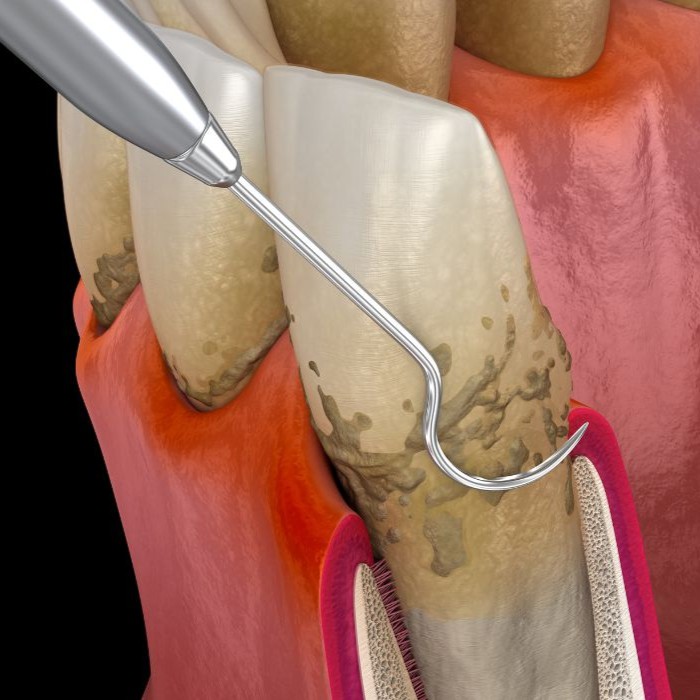

Le détartrage consiste à retirer mécaniquement le tartre accumulé sur les dents, au-dessus et légèrement en dessous de la gencive. Cette procédure simple et indolore est réalisée à l’aide d’ultrasons et d’instruments manuels. Elle permet de réduire les inflammations gingivales (gingivites), de prévenir la mauvaise haleine et de maintenir une bouche saine. Un polissage complète le soin pour lisser la surface des dents et retarder la réapparition du tartre.

Lorsque l’inflammation est plus avancée et que le tartre s’accumule sous la gencive, un surfaçage radiculaire peut être nécessaire. Ce soin consiste à nettoyer minutieusement les racines dentaires afin d’éliminer les dépôts bactériens et de lisser les surfaces radiculaires. Cela favorise la cicatrisation de la gencive, réduit les poches parodontales et limite la progression de la maladie parodontale.